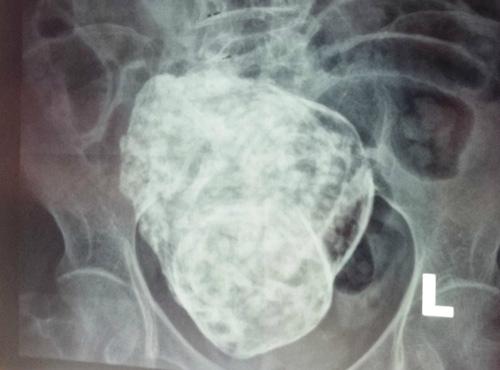

Để tìm ra chân tướng sự việc, bệnh viện đã mời một bác sĩ sản phụ khoa có thâm niên đến phụ trách kiểm tra. Sau khi thảo luận kỹ lưỡng, các bác sĩ đã đưa ra kết luận đáng ngạc nhiên: bào thai trong bụng bà Hoàng hóa ra là "bào thai đá" (Lithopedion). Đây là một hiện tượng hiếm gặp, xảy ra khi thai nằm trong ổ bụng bị chết và lưu lại trong cơ thể người mẹ lâu ngày rồi bị vôi hóa dần. Tỷ lệ thai trong ổ bụng khoảng 1/11.000 trường hợp thai kỳ, trong đó khoảng 1,5-1,8 % thai hóa đá.

Cụ thể hơn, các bác sĩ lý giải rằng: Bình thường trứng sau khi thụ tinh di chuyển và làm tổ trong buồng tử cung. Thai nhi sẽ tiếp tục phát triển để lớn lên. Tuy nhiên vì một lí do nào đó thai nhi bị chết và lưu lại trong cơ thể mẹ. Thường thì những thai nhi đó sẽ tự tiêu đối với những thai nhỏ, nhưng trong vài trường hợp một phần nào đó của thai nhi không thể tự tiêu hết mà phải nhờ đến sự hỗ trợ của bác sĩ. Tuy nhiên có vài trường hợp hiếm gặp thai nhi bị chết lưu không được loại bỏ hoàn toàn ra khỏi người mẹ. Theo thời gian thai nhi đó bị vôi hóa dần và trở thành thai đá.

Các bác sĩ suy đoán, có thể bà Hoàng đã từng mang thai một lần khi còn trẻ nhưng do nhiều nguyên nhân khác nhau, thai nhi không phát triển bình thường nên chết lưu. Trong tình huống bà hoàn toàn không nhận ra để loại bỏ khỏi cơ thể, bào thai đã trở thành "thai đá". Cú ngã này có thể đã vô tình đụng vào "thai đá", khiến bà bị đau bụng.